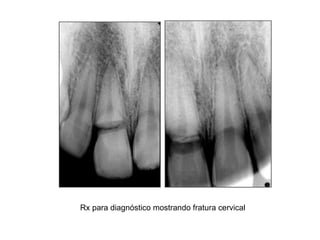

Rx para diagnóstico mostrando fratura cervical

Rx para diagnósticomostrando fratura cervical